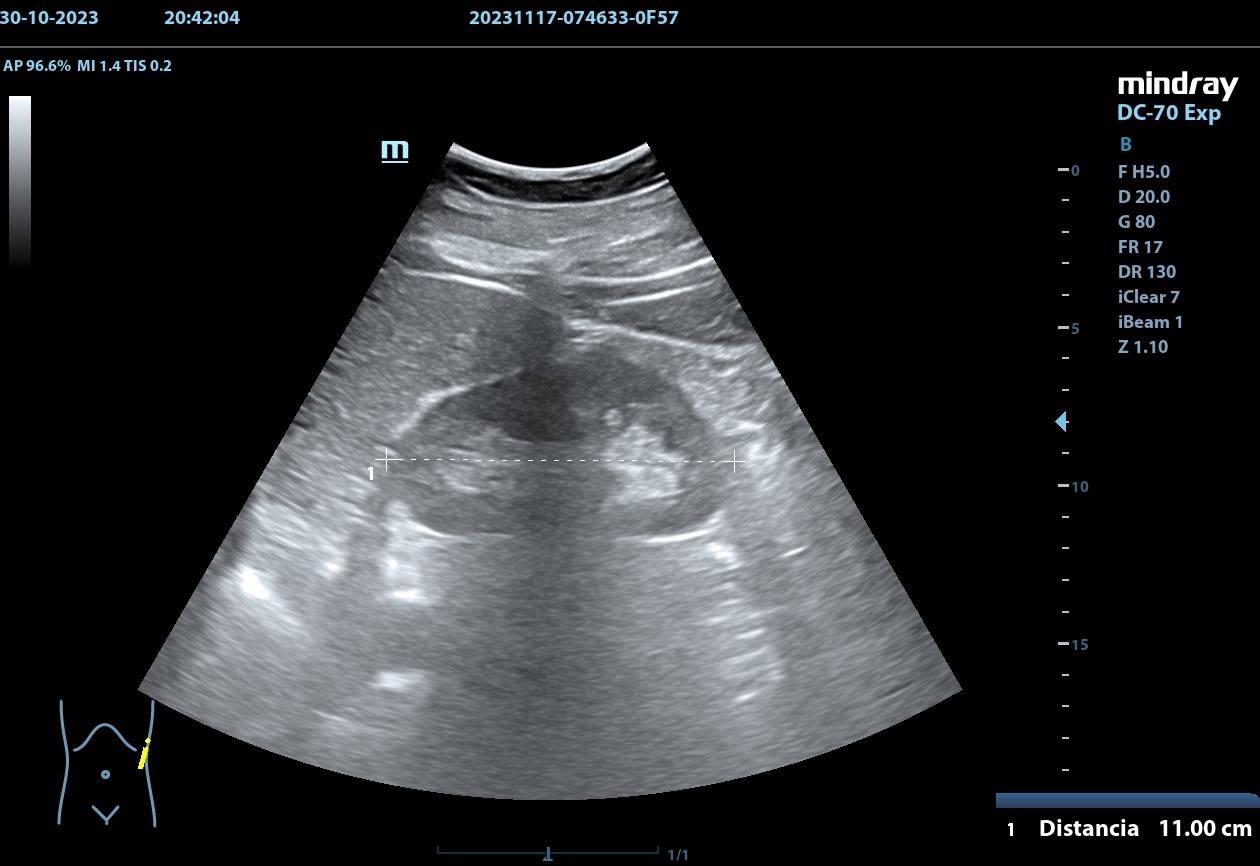

Hallazgos ecográficos

Se realiza, en consulta, una ecografía de las vías urinarias (POCUS), apreciando una lesión excrecente, pediculada, de 7,48 x 6,14 cm, que afecta a la pared izquierda y superior de la vejiga. Doppler negativo. No apreciándose jets ureterales. Riñón izquierdo de 11cm, y derecho de 9.27 cm, sin signos de dilatación de las pelvis renales que sugieran hidronefrosis.